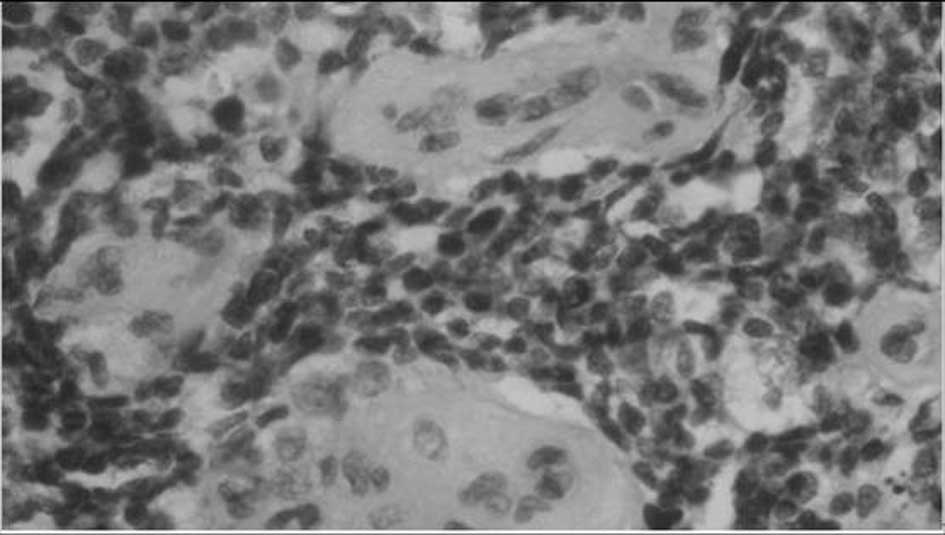

Primary dumbbell-shaped Ewing's sarcoma of the cervical vertebra in adults: Four case reports and literature review

Ewing's sarcoma is the second most common malignant bone tumor in children and adolescents. The 4 cases described in this study were diagnosed with dumbbell-shaped intraspinal and extraspinal Ewing's sarcomas. The incidence of dumbbell-shaped tumors of this type in the spine is 17.5%. These tumors are often misdiagnosed as neurogenic tumors (schwannoma, neurofibromatosis) or giant cell tumors based on imaging. Radiculopathy is more common than spinal cord compression in Ewing's sarcoma. Preoperative biopsy is strongly recommended. As soon as Ewing's sarcoma is diagnosed by pathology, the treatment should begin with 2-3 cycles of neoadjuvant chemotherapy. Anterior-posterior and posterolateral approaches are both recommended for exposing this tumor. Following surgery, chemotherapy is critical to lessen the rate of recurrence and metastasis and to prolong the survival time. However, radiotherapy should be used with caution, as the spinal cord is sensitive to radiation; local irradiation is suggested. The tumor is difficult to remove en bloc in the cervical spine. It has a high rate of recurrence and metastasis. Therefore, the prognosis of Ewing's sarcoma in the cervical region is poorer compared to that in the thoracic and lumbosacral regions.